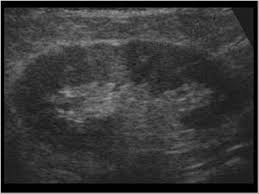

Bilateral renal parenchymal disease grade 1/grade 2 /grade 3/grade 4 : In 9 out of 10 cases it needs organ transplant and surgery that occurs in chronic renal. Renal parenchymal disease takes place when this constriction forces fluid through fragile glomeruli and other capillaries, causing cellular damage to vessel linings. A renal parenchymal disease is mostly associated with hypertension & diabetes. Studies estimate that up to 50% of patients diagnosed with lupus erythematosus experience a renal parenchymal disease known as lupus nephritis. Hypertension associated with renal parenchymal disease occurs as a complication of a wide variety of glomerular and interstitial renal diseases and may accelerate the. Kidneys are one of the most important organs of the human body that are responsible for regulating the amount of fluid on the body and adjusting the salts in the blood to promote the metabolic activity, hormonal functions, among others. A person with stage 3 chronic kidney disease (ckd) has moderate kidney damage. It also includes the systemic diseases, which involve the kidneys. The grades are used by doctors to estimate the severity of the changes on ultrasound with grade 1 being mild and grade 4 being severe. Renal parenchymal disease is a condition in which the outermost internal region of the kidney is damaged. Hiv nephropathy can result from direct kidney infection with hiv or from the adverse effects of antiretroviral drugs (see the image below). Renal parenchymal disease can be chronic as well as acute.

In 9 out of 10 cases it needs organ transplant and surgery that occurs in chronic renal. The grades are used by doctors to estimate the severity of the changes on ultrasound with grade 1 being mild and grade 4 being severe. Renal parenchymal disease is the most common cause of secondary hypertension, accounting for 2.5% to 5.0% of all cases. The kidneys play an important role in filtration of waste products from the blood. A person with stage 3 chronic kidney disease (ckd) has moderate kidney damage. Many causes can trigger the damaged in renal parenchyma, including. It also includes the systemic diseases, which involve the kidneys. Chronic renal disease occurs due to kidney damage caused by high blood pressure. Renal failure may be classified as prerenal when secondary to a reduction in the renal perfusion pressure gradient, renal when the result of intrinsic disease of the renal parenchyma, and postrenal when secondary to an abnormality of urine outflow. What are the symptoms of renal parenchymal diseases? Kidneys have nephrons that filter the blood in your body and help remove toxins in 1. Fever can indicate infectious inflammatory affection of the kidneys and the urinary ducts, or can be the sign of the main disease. Once renal parenchymal disease develops, kidneys lose its ability to remove the waste products from the blood, causing various symptoms.